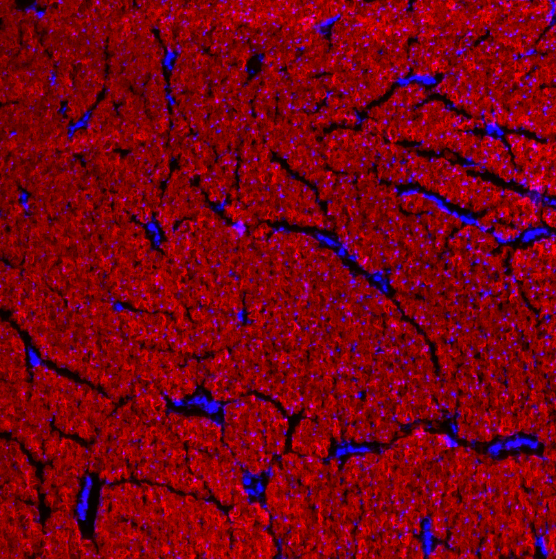

CHP is a powerful histopathology tool which enables straightforward detection of inflammation and tissue damage caused by a large variety of diseases, as well as tissue remodeling during development and aging. CHP robustly visualizes the pericellular matrix turnover caused by proteolytic migration of cancer cells within 3D collagen culture, without the use of synthetic fluorogenic matrices or genetically modified cells. CHP can measure and localize mechanical injury to collagenous tissue at the molecular level. It also enables assessment of collagen denaturation in decellularized extracellular matrix. In addition, CHP can be used to specifically visualize collagen bands in SDS-PAGE gels without the need for western blot.

Histopathology - unlock new insights in tissue damage: CHPs precisely detect and quantify denatured collagen, a hallmark of disease. CHPs are applicable to nearly all tissue types and a wide range of medical areas. More on histopathology...

- Collagen quantification - fluorescent quantification of total collagen: Total collagen staining with CHPs is made possible with a step-by-step guide with an Image-J / FIJI imaging protocol. More on collagen quantification...